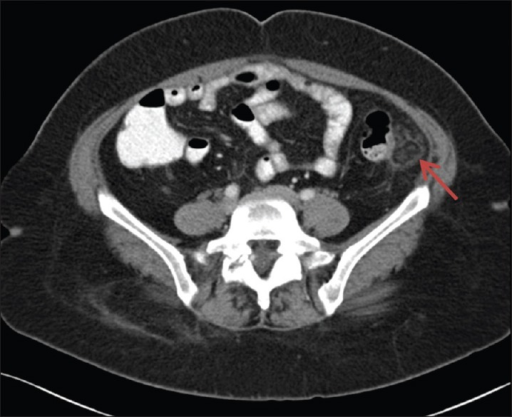

Puzzle 35

What's the Diagnosis?